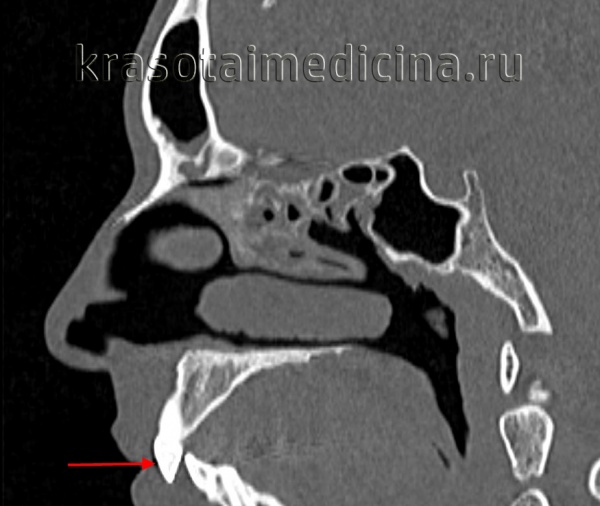

КТ черепа (3D-рендеринг). Прогнатический прикус, зубы верхней челюсти (красная стрелка) выстоят кпереди, отсутствует контакт резцовых краев при смыкании.

КТ черепа. Прогнатический прикус, зубы верхней челюсти (красная стрелка) выстоят кпереди (этот же пациент).